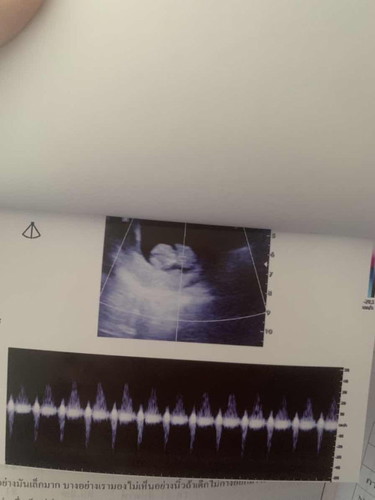

ซาวครั้งแรกเมื่อวานคะ 10+ 3 เห็นน้องแล้วคะอาหมอบอกน้องดูโตไวบำรุงอะไร แม่ไม่ได้บำรุงเลย แพ้ฉ่ำมากคะ เสียงหัวใจน้องชัดเจนมากคะ